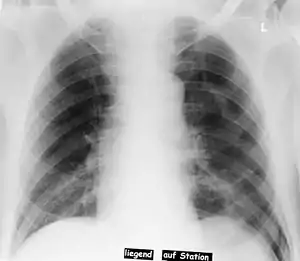

Deep sulcus sign

In radiology, the deep sulcus sign on a supine chest radiograph is an indirect indicator of a pneumothorax.[1][2] In a supine film, it appears as a deep, lucent, ipsilateral costophrenic angle[3] within the nondependent portions of the pleural space as opposed to the apex (of the lung) when the patient is upright. The costophrenic angle is abnormally deepened when the pleural air collects laterally, producing the deep sulcus sign.[4]

| Pneumothorax left sided | |

| Differential diagnosis | pneumothorax |

Patients with chronic obstructive pulmonary disease (COPD) may exhibit deepened lateral costophrenic angles due to hyperaeration of the lungs and cause a false deep sulcus sign.